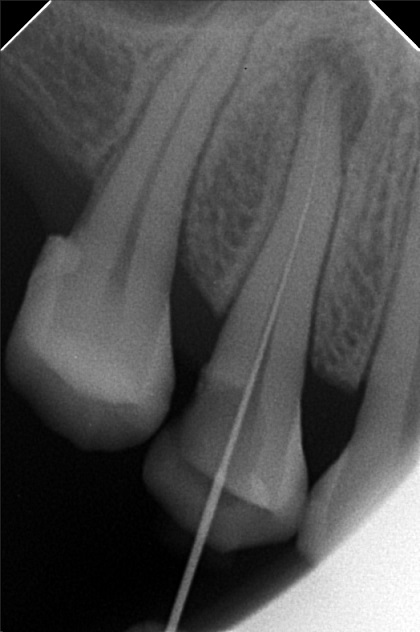

Edit Record Check our patient data records. Add patient information Patient Info Profile picture Last Name First Name Middle Name Birthdate Age Street Barangay City Country Zip Code Contact number Email Procedure 3/22/22- OP Lc 13 m/ 21 d/ 22 m/ 47 o/ b/ cervical xray 14 for rct 10/11/22 - OP (L); ACCESS #14, SCOUT #10 BL 18mm, EUGENOL. 10/14/22- 12/11/21/22- TF emax veneers 10/19/22 - 19mm, close w/ pulp devitalizer 09/02/23- op ** For change of crowns posterior Lower for Crown #15 08/13/24 OP 01/23/26 Alumina crwon #14 temporary crown OP Scanning File bangaros.jpg File 2 bongaros.jpg File 3 bongaros_02.jpg File 4 bongaros_03.jpg File 5 bongaros_04.jpg File 6 309497615_1081002115924778_349479569281481267_n.jpg File 7 bongaros_1.jpg File 8 bongaros_02_1.jpg File 9 File 10 File 11 File 12 File 13 File 14 File 15 File 16 File 17 File 18 File 19 File 20 Retain Record Retain Record Yes No Save Your Changes